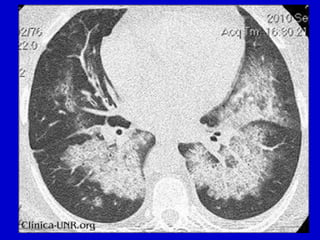

Sindrome de Goodpasture – Hemorragia pulmonar

Hemorragia pulmonar - Macroscopía

Hemorragia pulmonar - Microscopía

Examen Post morten de paciente con GNF Rápidamente Progresiva